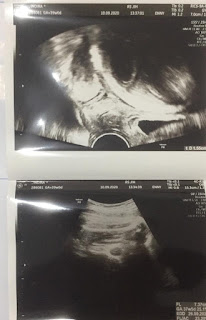

| USG pertama |

Kontrol lagi dengan beliau, beliau bilang, “nah ini dia bayinya, kemarin ngumpet nih, dengan kondisi kantung yg sudah besar kemarin seharusnya janinnya sudah ada tapi kemarin blm keliatan, sekarang udah jelas nih ada, besar janinnya sudah pas, sehat”. Kayaknya beliau gamau ngasih tau pas USG kemarin deh, takut jadi pikiran hahaha alhamdulillaah dan beliau menyarankan untuk kontrol bulan depan lagi.

![]() |

| USG kedua week 7 |

| USG adek umur 20 weeks |

| USG terakhir adek |